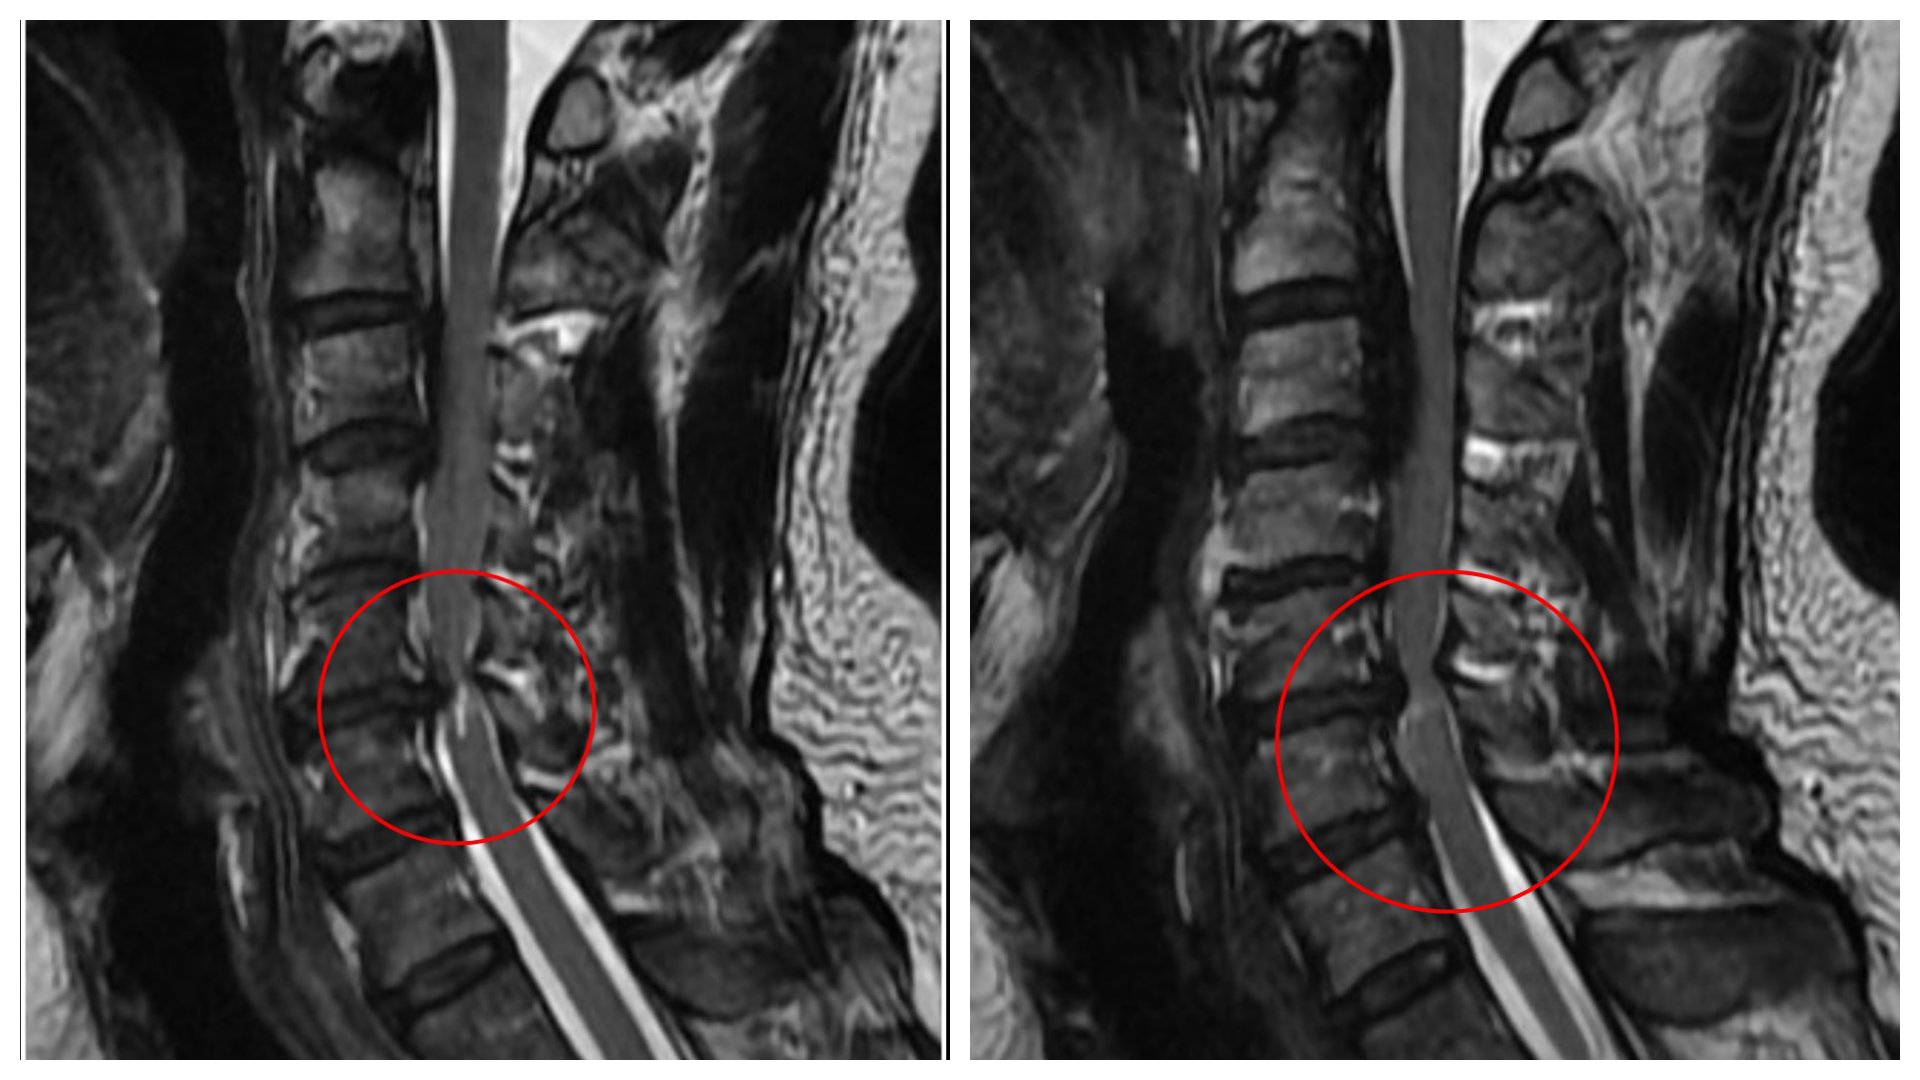

黃先生的頸椎第二節到第六節都有後縱韌帶骨化,其中第五、六節最為嚴重,脊髓已被壓得非常狹窄,核磁共振更可見明顯脊髓空洞,洪祥益主任說,這代表神經已受損,必須盡快手術,若再拖延,一旦跌倒、車禍或頸部突然甩動,都可能造成急性脊髓傷害,增加癱瘓風險。